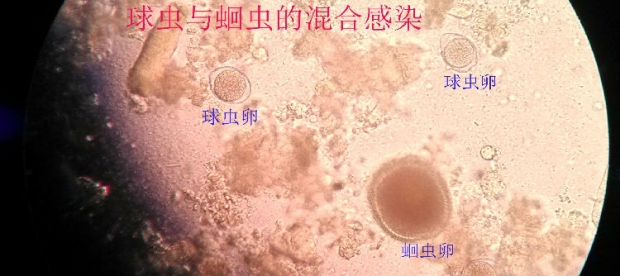

犬猫球虫病 郑州宠物医院 郑州动物医院 郑州最好的宠物医院

猫球虫病症状图片 图鉴 兽药招商网

关于犬猫球虫病的详细介绍 狗狗常见病 波奇网百科大全